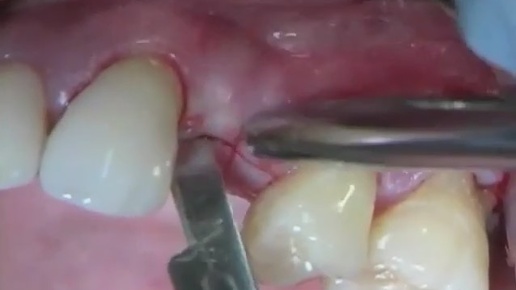

Как ставят импланты зубов - полная процедура пошагово